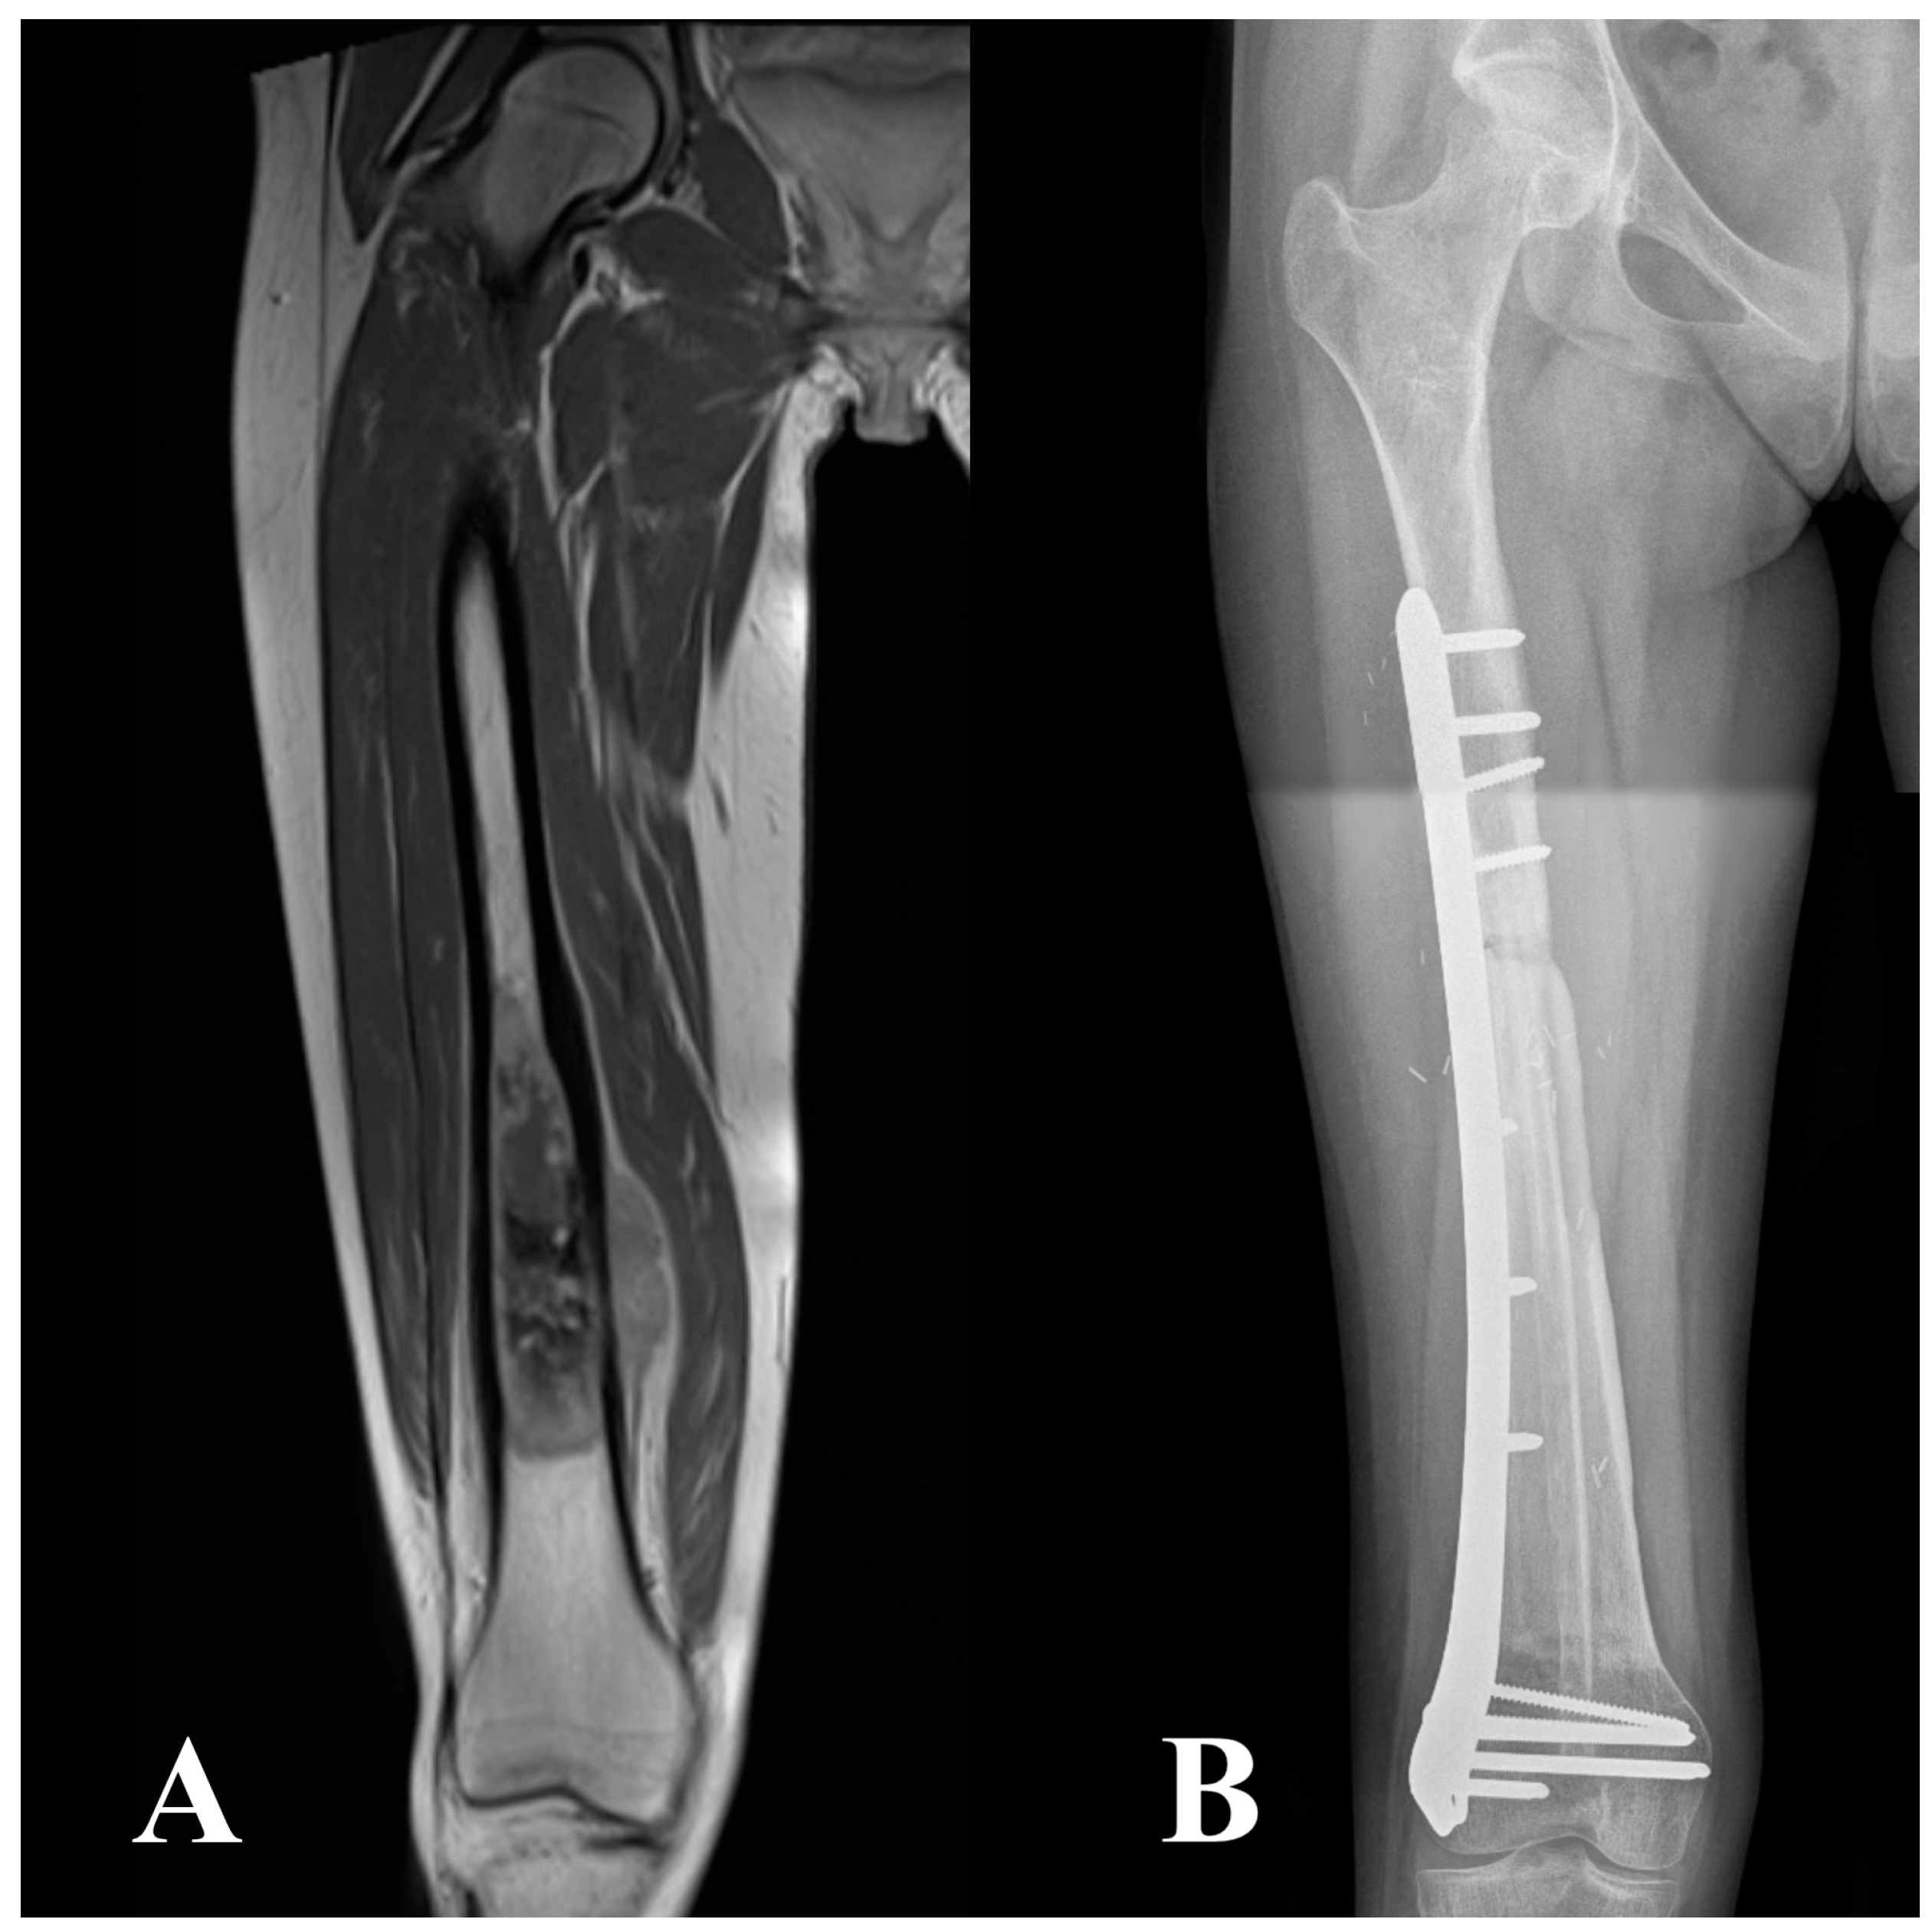

2.2. Surgical Technique, Aftercare, and Cancer Treatment

| Intercalary | 77 (10) | 58 (15) |

| Intraepiphyseal | 23 (3) | 42 (11) |

| Fixation method | ||

| Single bridging plate | 77 (10) | 35 (9) |

| Metaphyseal screws + diaphyseal plate | 15 (2) | 42 (11) |